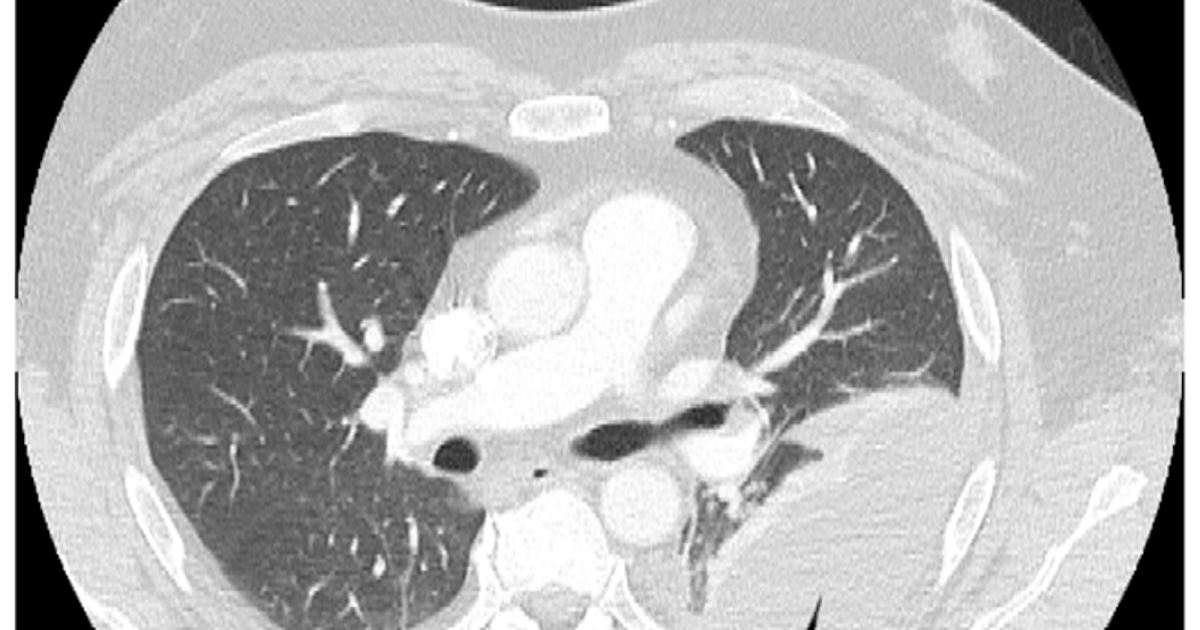

Loculated Pleural Effusion Ct : Rather than layering laterally and blunting of the costophrenic angle, the pleural fluid lies almost exclusively betw.. Subpulmonic effusions (also known as subpulmonary effusions) are pleural effusions that can be seen only on an erect projection. Rather than layering laterally and blunting of the costophrenic angle, the pleural fluid lies almost exclusively betw. However, it is not practical to recommend ultrasonography for all effusions. Jun 05, 2012 · thoracentesis in small or loculated pleural effusions, thereby increasing the yield and safety of the procedure.